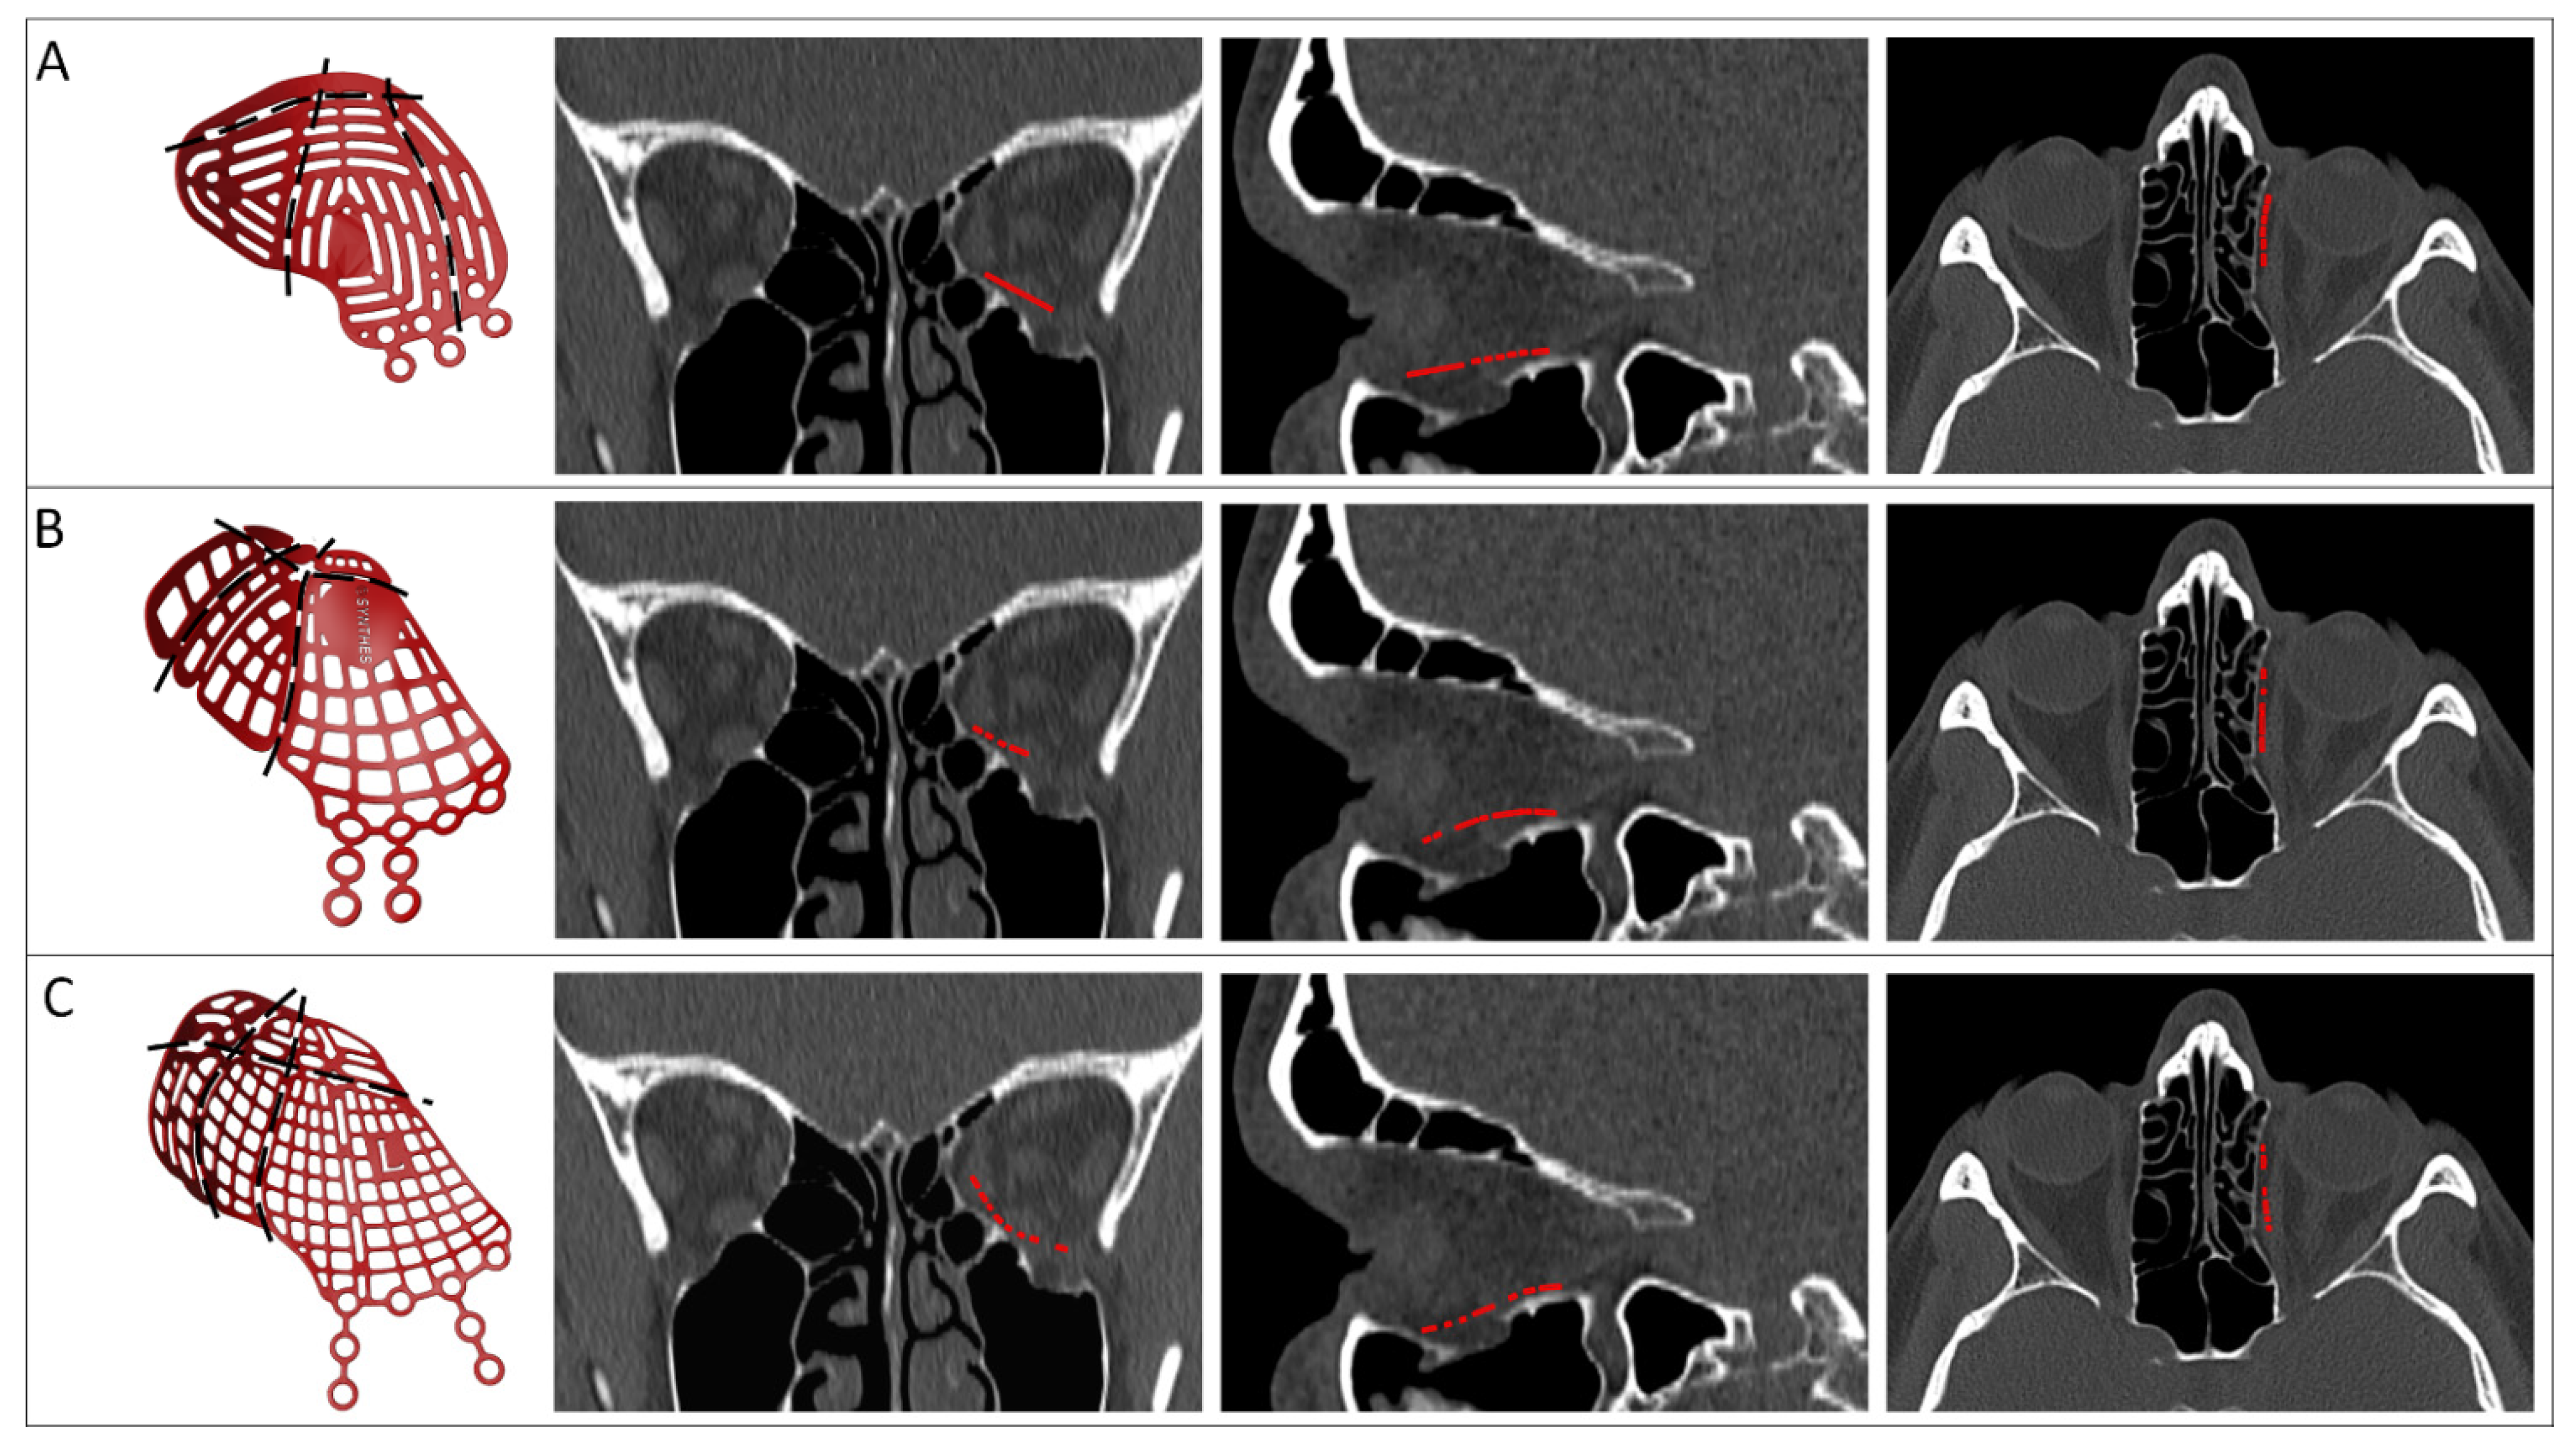

| Design Consideration | Effect on | Options | References | Notes |

|---|---|---|---|---|

| Thickness | Positioning, stability | 0.3 mm | [22,37,38] | |

| Atraumatic cord | Positioning, stability | Present | [37,39,40] | |

| Absent | [38,41,42] | |||

| Grid | Clinical symptoms | Horizontal | [22,37,40,43] | |

| Squares | [38,39,41,44] | |||

| Porous | [42,45,46] | |||

| Support | Stability, accuracy | Three points | [22] | Infraorbital rim, medial wall, posterior ledge |

| [38] | Anteromedial, anterolateral, posterior | |||

| Ledge | [37,40,43] | Inverted shovel design | ||

| Lateral posterior wall | [43] | Stabilizer for self-centering implant | ||

| Extension | Accuracy | Orbital rim | [22,42,44,46,47,48] | |

| Lateral posterior wall | [43] | |||

| Specific bone features | [45] | |||

| Anterior elevation | Clinical symptoms | [22] | Rim elevation to correct hypoglobus | |

| Overcorrection | Clinical symptoms | Location | [22] | Posterior to bulbus |

| [49] | Orbital floor elevated in sagittal relation | |||

| Amount | [22] | Based on clinical findings, advanced diagnostics | ||

| [38] | Slight overcorrection | |||

| [50] | Same amount in cubic cm as mm enophthalmos | |||

| Intraoperatively | [51] | Spacers | ||

| Navigation | Accuracy | Markers | [22,37,38,39,52] | Eminence lacrimal foramen [38] |

| Vectors | [37,40,43] | |||

| Fixation | Stability | Absent | [38,44,48] | |

| Present | [22,37,39,40,42,46,47,53] | Eccentric screw alters implant position [47] Fix implant if form stable [40] | ||

| Fixation re-use | Accuracy | Re–used screw hole | [54] | Only in secondary reconstruction |

| Multi-piece | Positioning, stability, | Lazy-S | [42,47,49] | |

| accuracy | Interlocking | [46,48,55,56] |